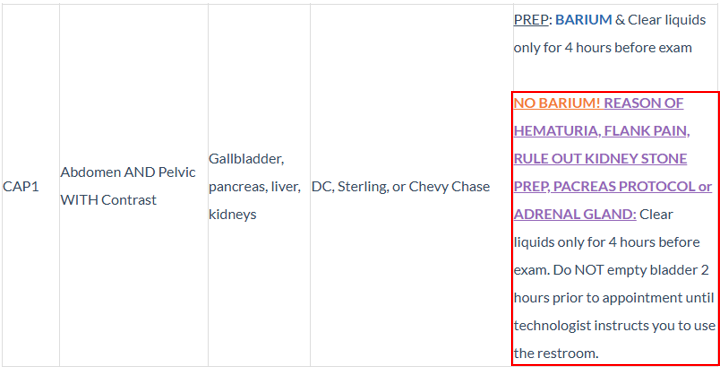

- Patient is scheduling a CT Abdomen & Pelvic WITH Contrast and the reason for the exam is hematuria and flank pain...

- Merge Prep Instructions will reflect the following information...

- BUT...since the reason for exam is hematuria and flank pain, we should provide the prep instructions listed in the Playbook...

- NOTE: This information is also available on the CT Exam Warning that populates just before the Questionnaire...